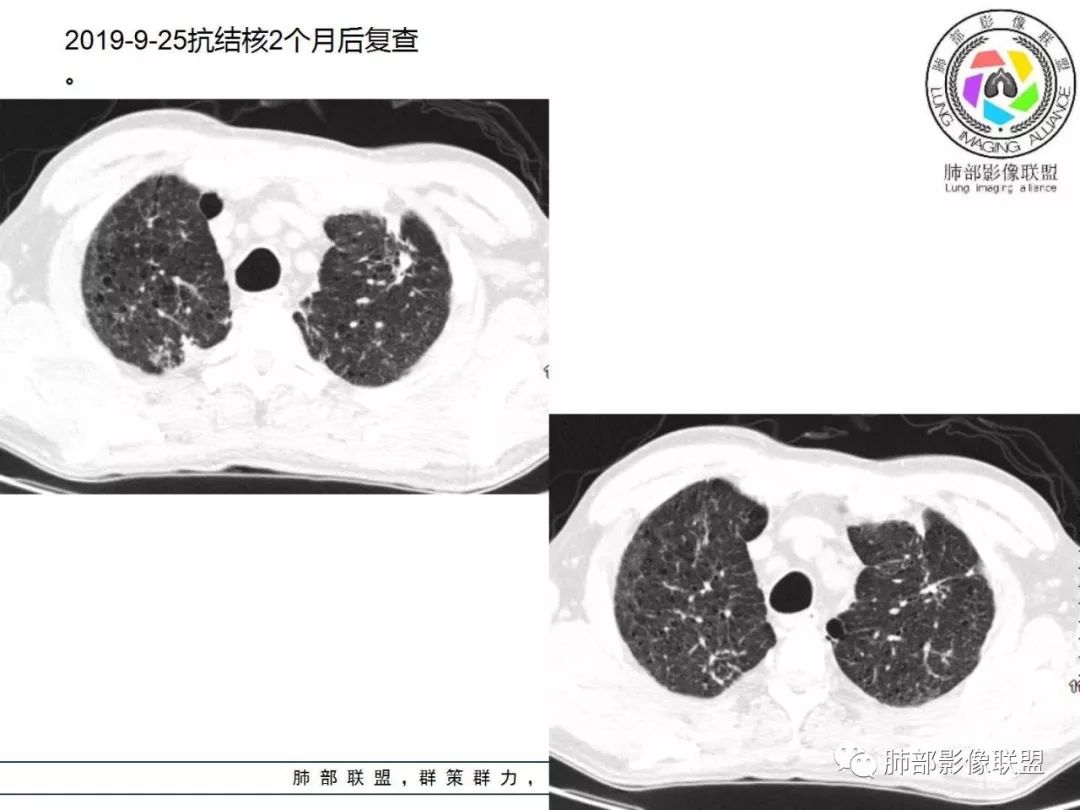

答案揭晓

04

间质性肺结核

1. 老年男性,发热为主诉,体温38°-39°,发热以午后及晚上为主,伴黄痰,CRP增高,临床病史支持感染性病变;

2. 肺气肿背景(小叶中心性肺气肿);双肺多发病灶整体沿血管支气管束及胸膜下分布,以上叶及下叶背段分布为主,有实变及GGO,边界清楚,有树芽,小叶间隔及中央间质增厚,叶间裂见到多发结节,部分支气管不规则牵拉扩张,提示病灶纤维化明显,结合临床病史,考虑病灶为间质性感染,肺门及纵隔内有钙化淋巴结,小叶间隔结节,考虑淋巴道增值性疾病可能,综合常规要怀疑间质性肺结核。

3. 该病例临床提示感染,有支气管扩张,提示纤维化,需要与感染后的OP鉴别,但是OP病灶常无结节感;间质性肺结核有时与不典型结节病鉴别也比较困难,结节病常以双肺门淋巴结增大为特征。临床上结核发病率较高。